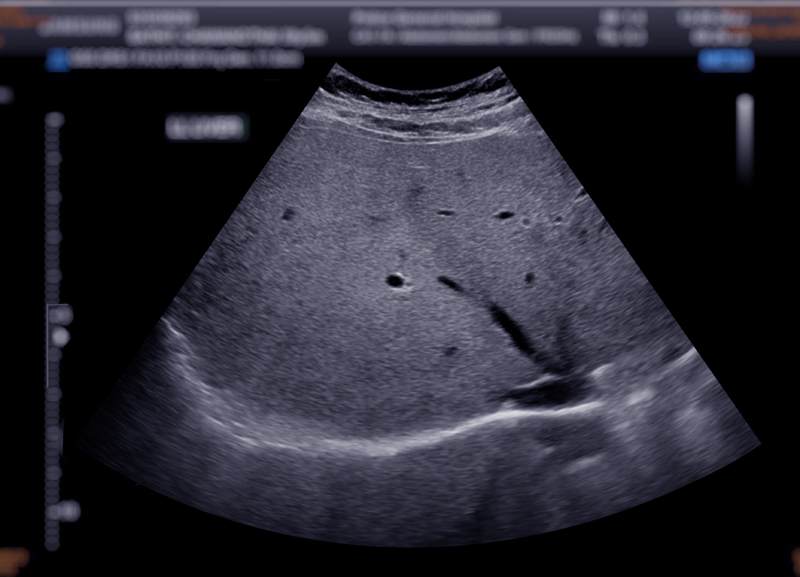

影像已经在提示异常

来源:摄图网

在超声检查中,“低回声”“异常回声”是非常常见的描述,常见于甲状腺、乳腺、肝脏等部位。它本质上反映的是,该区域的声学特征与周围正常组织存在差异,也就是说,影像已经发现这里“有些不一样”。

需要明确的是,这种“不一样”并不等于癌症。很多良性病变,如炎症、增生、囊性改变等,也可能表现为低回声或异常回声。但从医学判断逻辑来看,这类表现也绝不会是“随机出现”的正常现象,而是提示需要进一步分析的信号。

在临床评估中,医生通常不会单独根据“回声”来判断风险,而是需要结合多个维度进行综合判断,比如:

边界是否规则

内部回声是否均匀

是否伴随血流信号

是否存在钙化等

这些特征组合在一起,才构成影像学上的风险判断依据。以乳腺和甲状腺为例,通常还会通过BI-RADS或TI-RADS等分级系统,对病变进行标准化风险评估,并给出随访或进一步检查的建议。